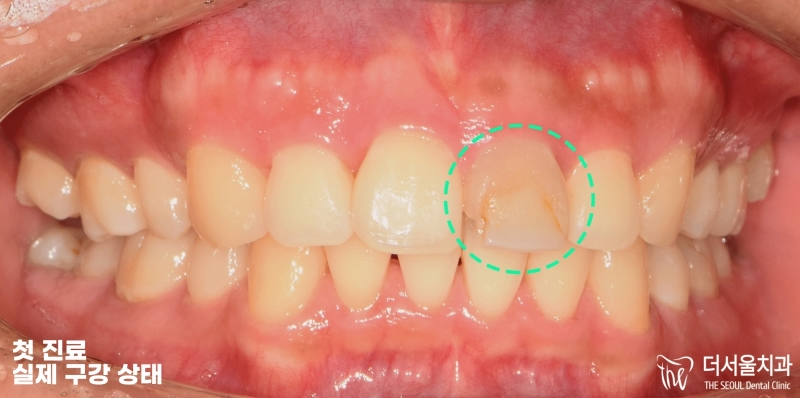

안녕하세요, 박현준 원장입니다. 오늘 보여드리는 임상 증례는, 크라운 수복으로 앞니 라미네이트 치료 처럼 한 임상 케이스입니다. 아래 사진으로